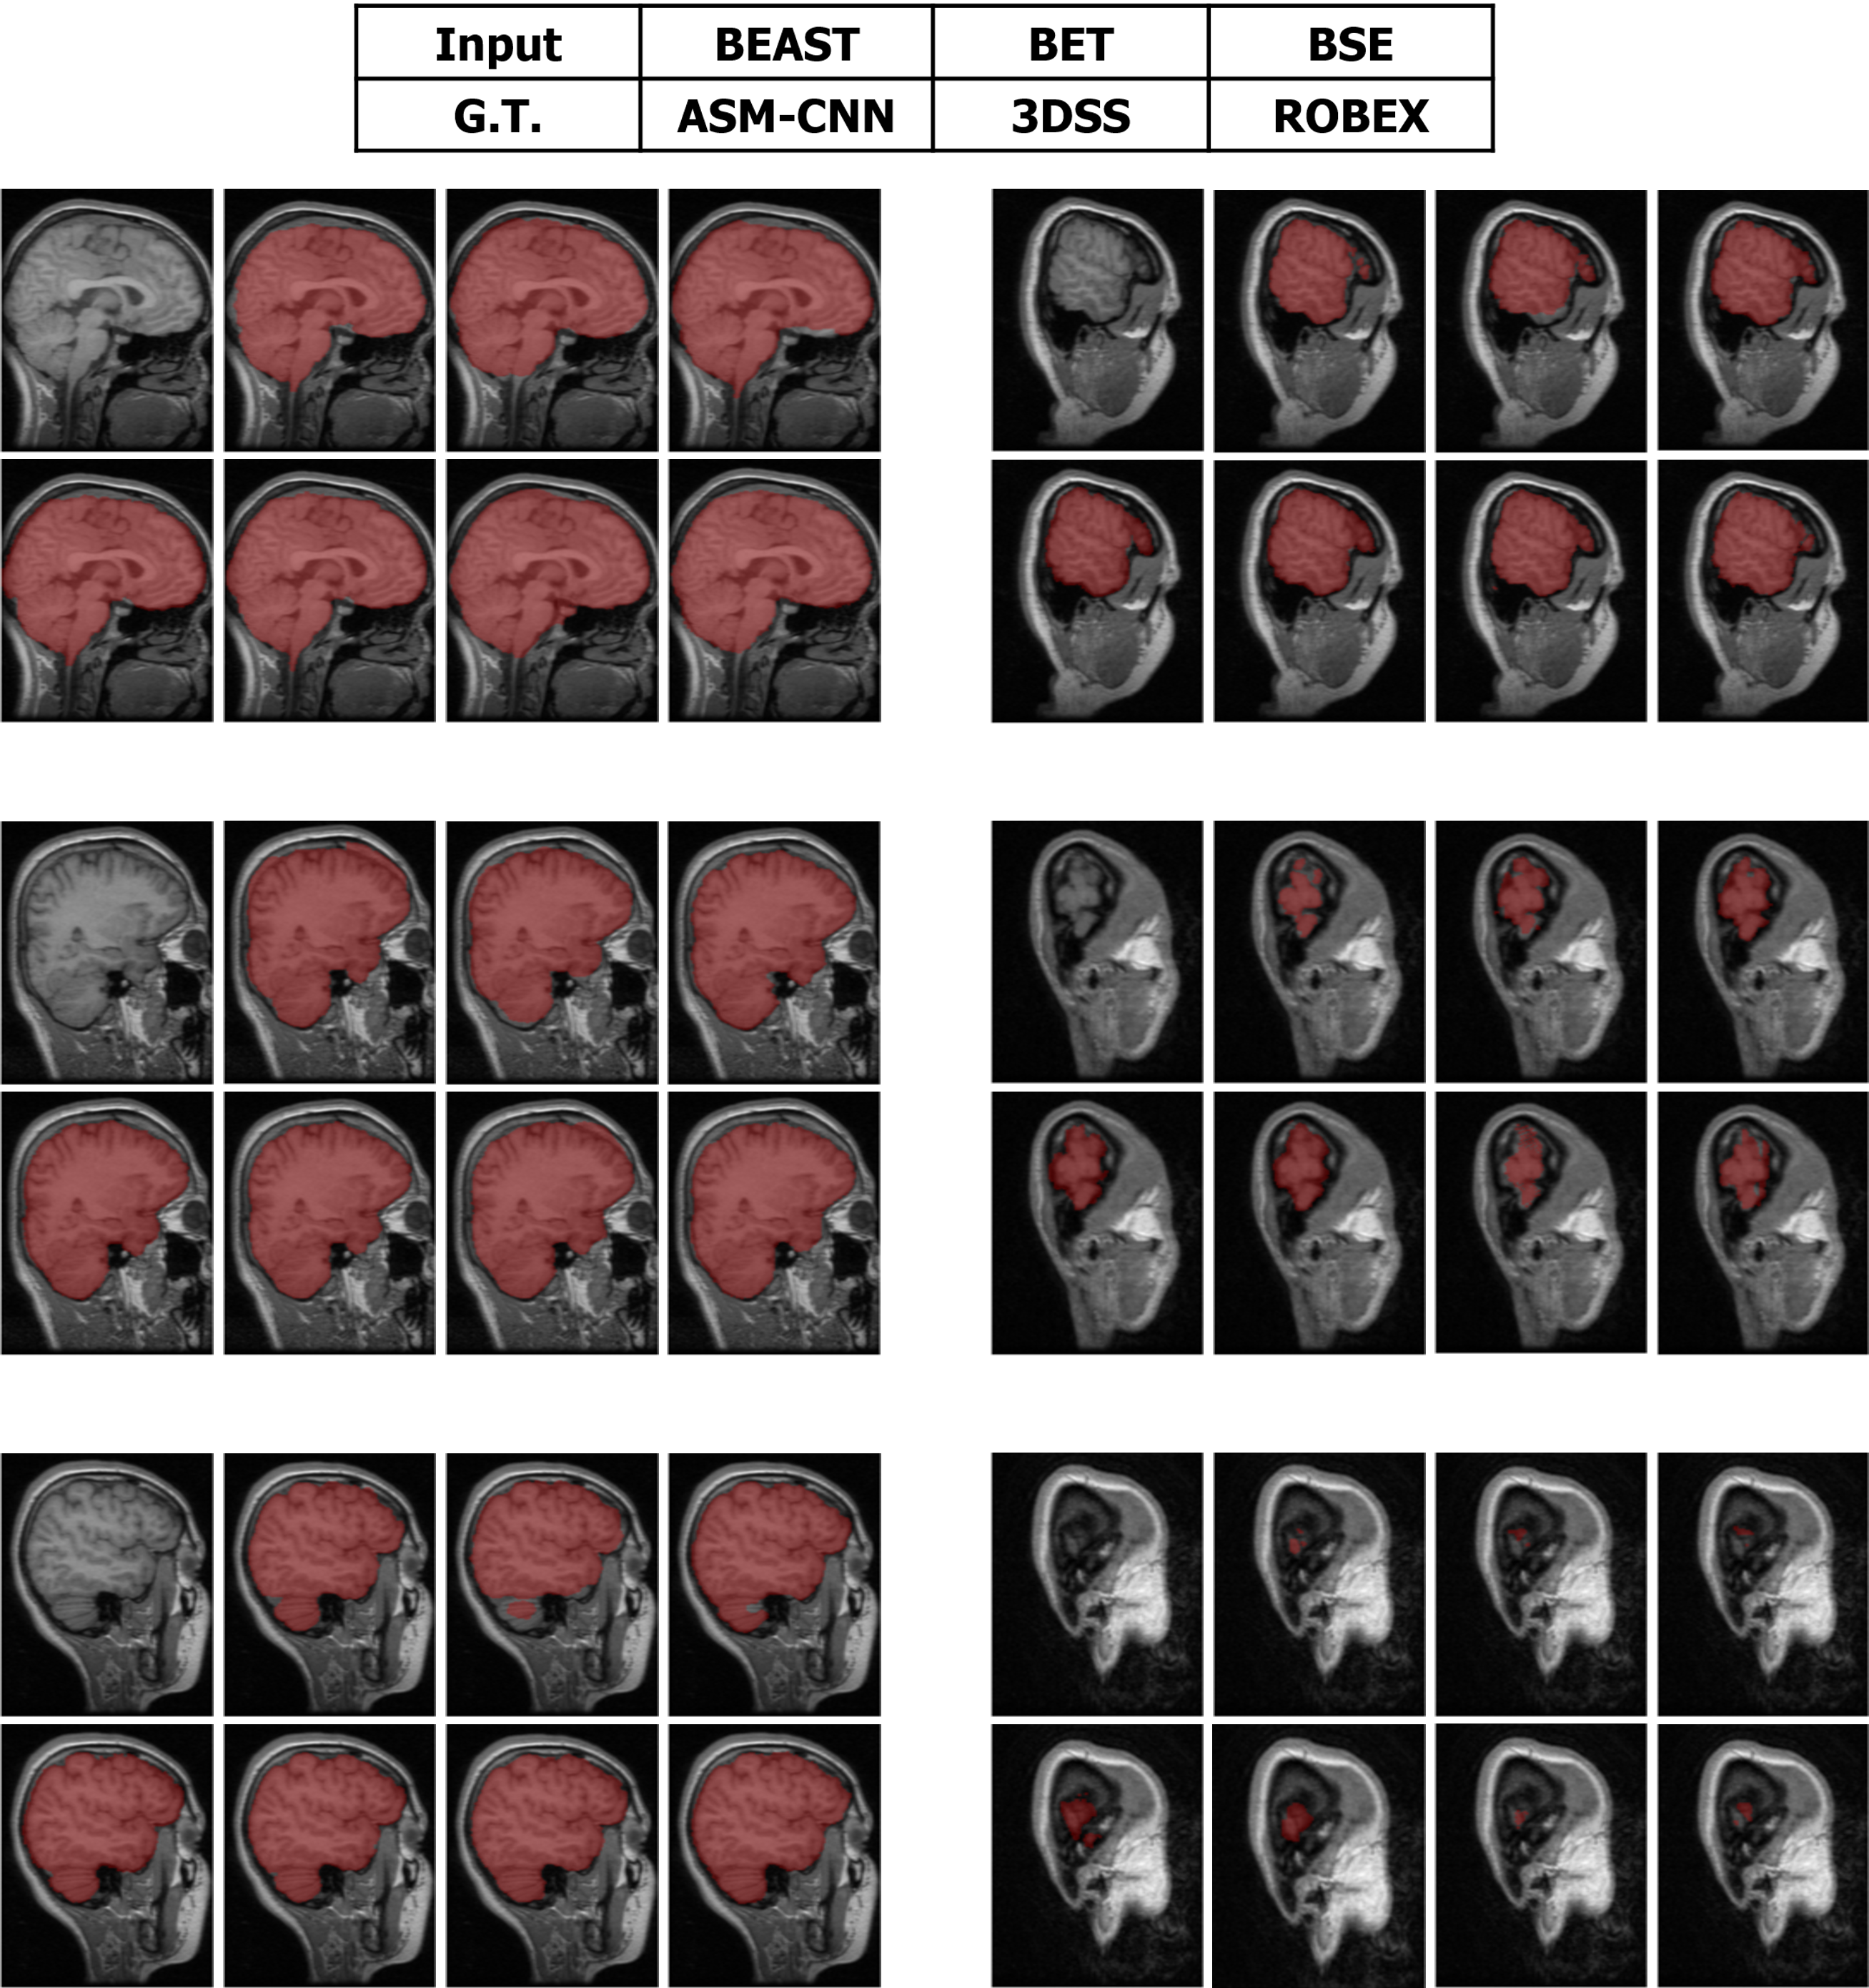

Refer to caption

Figure 11: The comparison between ASMCNN with other methods on IBSR dataset.

Segmentation results of ASMCNN and seven other methods in the sagittal plane for the three datasets are illustrated in Figures 11, 12 and 13 respectively. Each figure includes six typical testing scans from all three groups (two scans for each group). Although ASMCNN works with the sagittal plane, it also produces correct segmentation in two other planes. Figure 14 shows the comparison between our approach and other methods on each dataset for these two planes.

Figure 12: The comparison between ASMCNN with other methods on OASIS dataset.

Figure 13: The comparison between ASMCNN with other methods on LPBA dataset.

ASMCNN can provide extremely accurate segmentation in these three datasets. We achieve the same results as ROBEX with smooth boundaries and keep both gray and dura matter inside extracted brains for most cases, which are usually left out by ROBEX. Although there are minor leakages into the skull by ASMCNN, its occurrence is less than both ROBEX and BEAST, as it only generates a smaller number of over-segmentation results. The critical impact of the method is that it can precisely work for small-size brains in Group I as well, meanwhile other techniques usually fail. As shown in Figures 11 - 13, our results are mostly similar to the ground-truth images especially for tiny-size brains (Figure 11). The method does not avoid a few false negatives and false positives in this group on account of the complexity of the brain structure. Nevertheless, ASMCNN can mostly obtain a better performance than others with higher accuracy.